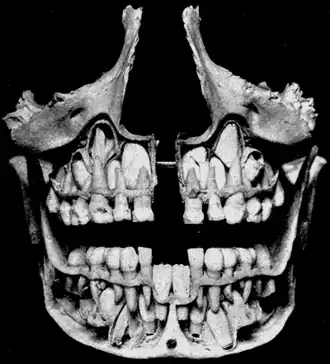

![]() Детский череп, постоянные зубы заменяют молочные. | |

Моло́чные зу́бы — первый комплект зубов у людей и многих других млекопитающих.

У человека прорезываются 20 молочных зубов: по 10 на верхней и нижней челюстях, по 5 на каждой половине челюсти (два резца, клык и два моляра).

Период сохранения молочных зубов и прорезывания постоянных называют периодом сменного прикуса — после выпадения молочного зуба до прорезывания постоянного обычно проходит 3-4 месяца. В дальнейшем последовательность смены зубов примерно соответствует прорезыванию молочных зубов. В возрасте 11 лет прорезываются вторые моляры. К 12-13 годам формируется постоянный прикус. Третьи моляры (зубы мудрости) прорезываются в возрасте 17—25 лет или позже либо вообще не прорезываются. У девочек прорезывание зубов происходит несколько раньше, чем у мальчиков.